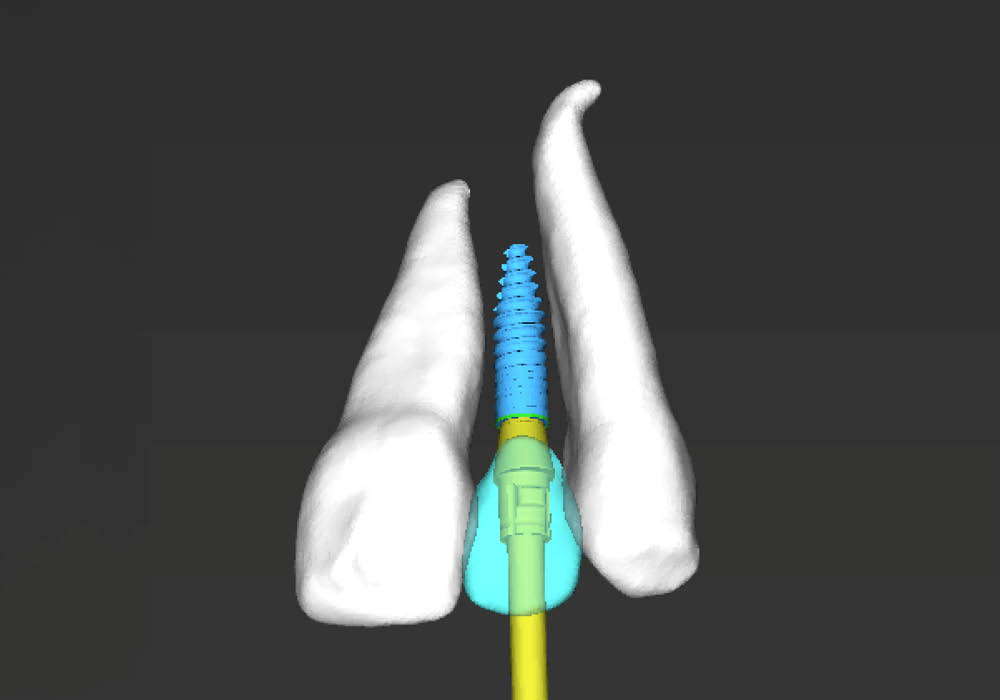

3. Pianificazione chirurgica

La pianificazione chirurgica ha previsto un’analisi tridimensionale dettagliata del sito implantare, valutato sia da angolazioni multiple sia in visione frontale diretta.

L’obiettivo era quello di definire con precisione posizione, profondità e inclinazione dell’impianto, tenendo conto della vicinanza delle radici adiacenti e della necessità di preservare un adeguato spessore vestibolare.

Questa fase ha permesso di anticipare eventuali criticità e assicurare l’inserzione corretta all’interno dei limiti anatomici disponibili.